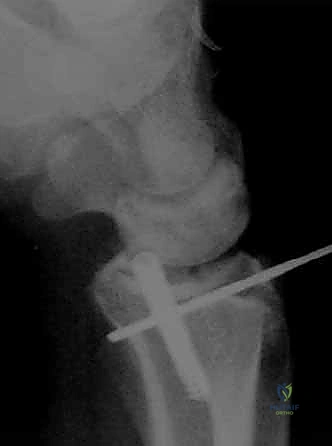

الخطوة الخامسة: التثبيت الداخلي

بمجرد استعادة الشكل التشريحي، يتم تثبيت العظام. قد يتم استخدام أسلاك كيرشنر (K-wires)، مسامير دقيقة، أو شريحة معدنية داعمة (Volar Plate) توضع من خلال شق صغير منفصل لضمان ثبات الكسر التام. يتم أيضاً خياطة أي تمزق في الأربطة إن وجد.

يتم تحديد خطة العلاج من قبل الأستاذ الدكتور محمد هطيف بناءً على تقييم دقيق للصور الشعاعية (X-ray) والأشعة المقطعية (CT scan) لمعرفة مدى تفتت الكسر وتأثر السطح المفصلي.